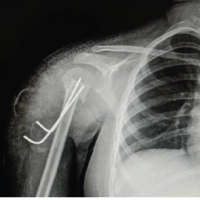

The patient in this report is a 40-year-old African American male with no active systemic disease. At the age of 25, he was found to have proteinuria, which led to a diagnosis of focal segmental glomerulosclerosis (FSGS) after a complete investigation. At that time, he was treated with ACE inhibitors and after about 2 years, his labs had normalized, and treatment was discontinued by his nephrologist. He denies any further medical issues since that time and currently has no diagnosis of kidney disease, diabetes mellitus, or autoimmune disorders. He is a former college football player and states that over the last year or so, he has begun working out heavily again, running, lifting weights and cycling. He denies any history of chronic steroid use, recent antibiotic use, or antecedent knee pain prior to this injury. He presented to the emergency department of a level 1 trauma center for further evaluation of bilateral knee pain after falling backward with his knees in a flexed position while wrestling at a charity event. He describes running at full speed and then planting his feet to jump when he experienced immediate bilateral knee pain, fell to the ground, and was unable to ambulate. The diagnosis of bilateral patellar tendon ruptures was made radiographically and clinically after imaging was obtained, and the patient was evaluated in the emergency department. AP and lateral radiographs of the bilateral knees demonstrate bilateral patella alta, according to the Insall-Salvati ratio (ISR) (1.77 on the right and 1.8 on the left), as shown in Figs. 1 and 2. On clinical examiation, the patient was unable to perform a straight leg raise bilaterally, indicating disruption of the knee’s extensor mechanism; he also had palpable defects in the anterior knee where the patellar tendon is typically present and a high riding patella bilaterally. With bilateral extensor mechanism injuries, the need for surgical intervention was explained to the patient, who agreed to this plan. He was placed in bilateral knee immobilizers and admitted to the hospital for surgical repair. Two days after admission, he was taken to the OR by the orthopedic surgery trauma team.

Both wounds were closed in a layered fashion with #1 Vicryl followed by 0 Vicryl to repair the deep fascia, 2-0 Vicryl to repair deep dermal layers, and staples to repair skin. The patient was then placed in a sterile compression absorbent dressing and bilateral knee immobilizers. He was made weight bearing as tolerated with the knee immobilizers in place. Postoperative imaging demonstrates improved and appropriate alignment of the bilateral patellas (Figs. 7 and 8). He recovered in the hospital as expected, began ambulating with physical therapy on postoperative day 1 and was discharged to acute rehab on postoperative day 5. Patient lives in a different state than the one where his surgery was performed and will follow-up with an orthopedic surgeon in his hometown.